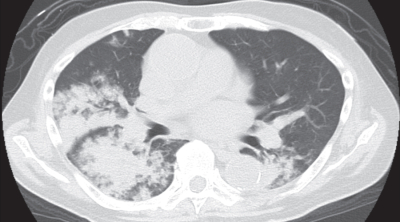

血液所見:白血球9,800(好中球91%、好酸球0%、単球5%、リンパ球4%)。CRP 4.0mg/dL。動脈血ガス分析(鼻カニューラ0.5L/分 酸素投与下):pH 7.33、PaCO2 58Torr、PaO2 62Torr、HCO3- 30mEq/L。肺野条件の胸部CTと喀痰Gram染色標本を別に示す。